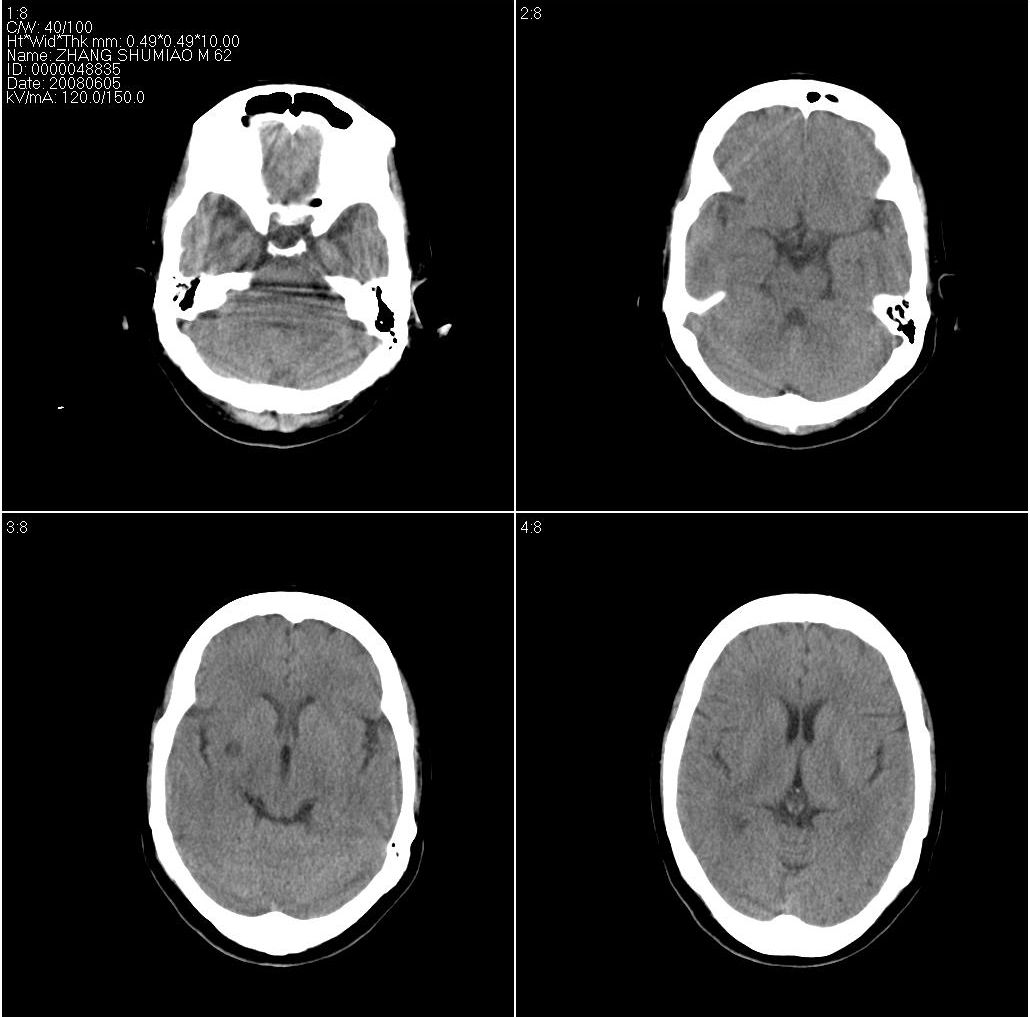

以下是引用欧阳双全在2008-6-5 16:37:00的发言:[br]小类圆形低密度影,边界清,考虑为外囊区腔隙性脑梗塞!

以下是引用zjzjr在2008-6-5 17:32:00的发言:[br]右侧基底节腔隙性梗塞!